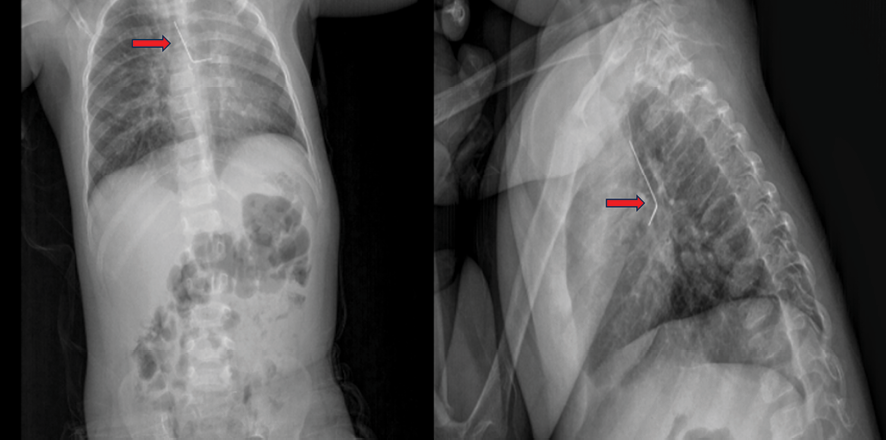

A 19-month-old female was admitted to another hospital with a persistent cough complaint. The foreign body was identified on a chest X-ray. Due to the absence of a pediatric surgeon, the patient was referred to our clinic and subsequently admitted to our care. History of the patient known to have a suspected grape allergy. Her vitals were hemodynamically stable. Oxygen saturation was between 97%-100% at room air. A physical examination revealed diminished breath sounds accompanied by mild wheezing. Laboratory findings were unremarkable. The initial chest X-ray revealed the presence of a foreign object, shaped like an ‘L’, lodged in the left bronchial tree (Figure-1).

Figure 1. Chest X-ray (the red arrow points to the L-shaped pin)